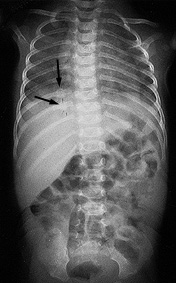

| Figure 1:Metaphyseal Bucket Handle Fracture | Figure 2:Posterior Rib Fracture |

Image used with permission from David Pressel, MD, PhD, Nemours/A.I. duPont Hospital for Children. |

Metaphyseal fractures are considered to be pathognomonic for abuse. These fractures are subtle findings on radiographs, often appearing as chips or fractures from the corner of the bone known as "bucket handle" fractures.37 (See Figure 1.) This type of fracture is particularly important to detect, as injury to the metaphyseal plate may limit future growth if not adequately treated in a timely manner.3

Rib fractures account for up to 27% of all abusive skeletal injuries45 and occur as a result of direct blows, as well as anteroposterior compression of the chest wall, such as occurs when holding and shaking an infant. Most abusive rib fractures are posterior and adjacent to the vertebral body, due to the leveraging of forces over the transverse process of the vertebra.37 (See Figure 2.) To diagnose these difficult-to-detect fractures, skeletal surveys are recommended in children younger than age 2 in whom abuse is suspected. Radionuclide bone scanning or repeat skeletal surveys within two weeks may detect new rib fractures and subtle long bone fractures not evident on skeletal survey.1,49